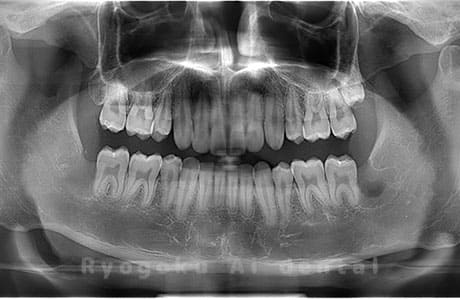

Case03

-

- 原因

- 上顎、下顎の親知らず

- 治療内容

- 上下4本の親知らずを抜歯したケースです。

<リスク・副作用>

手術後は痛み、腫れ、痺れなどの副作用が生じる場合があります。